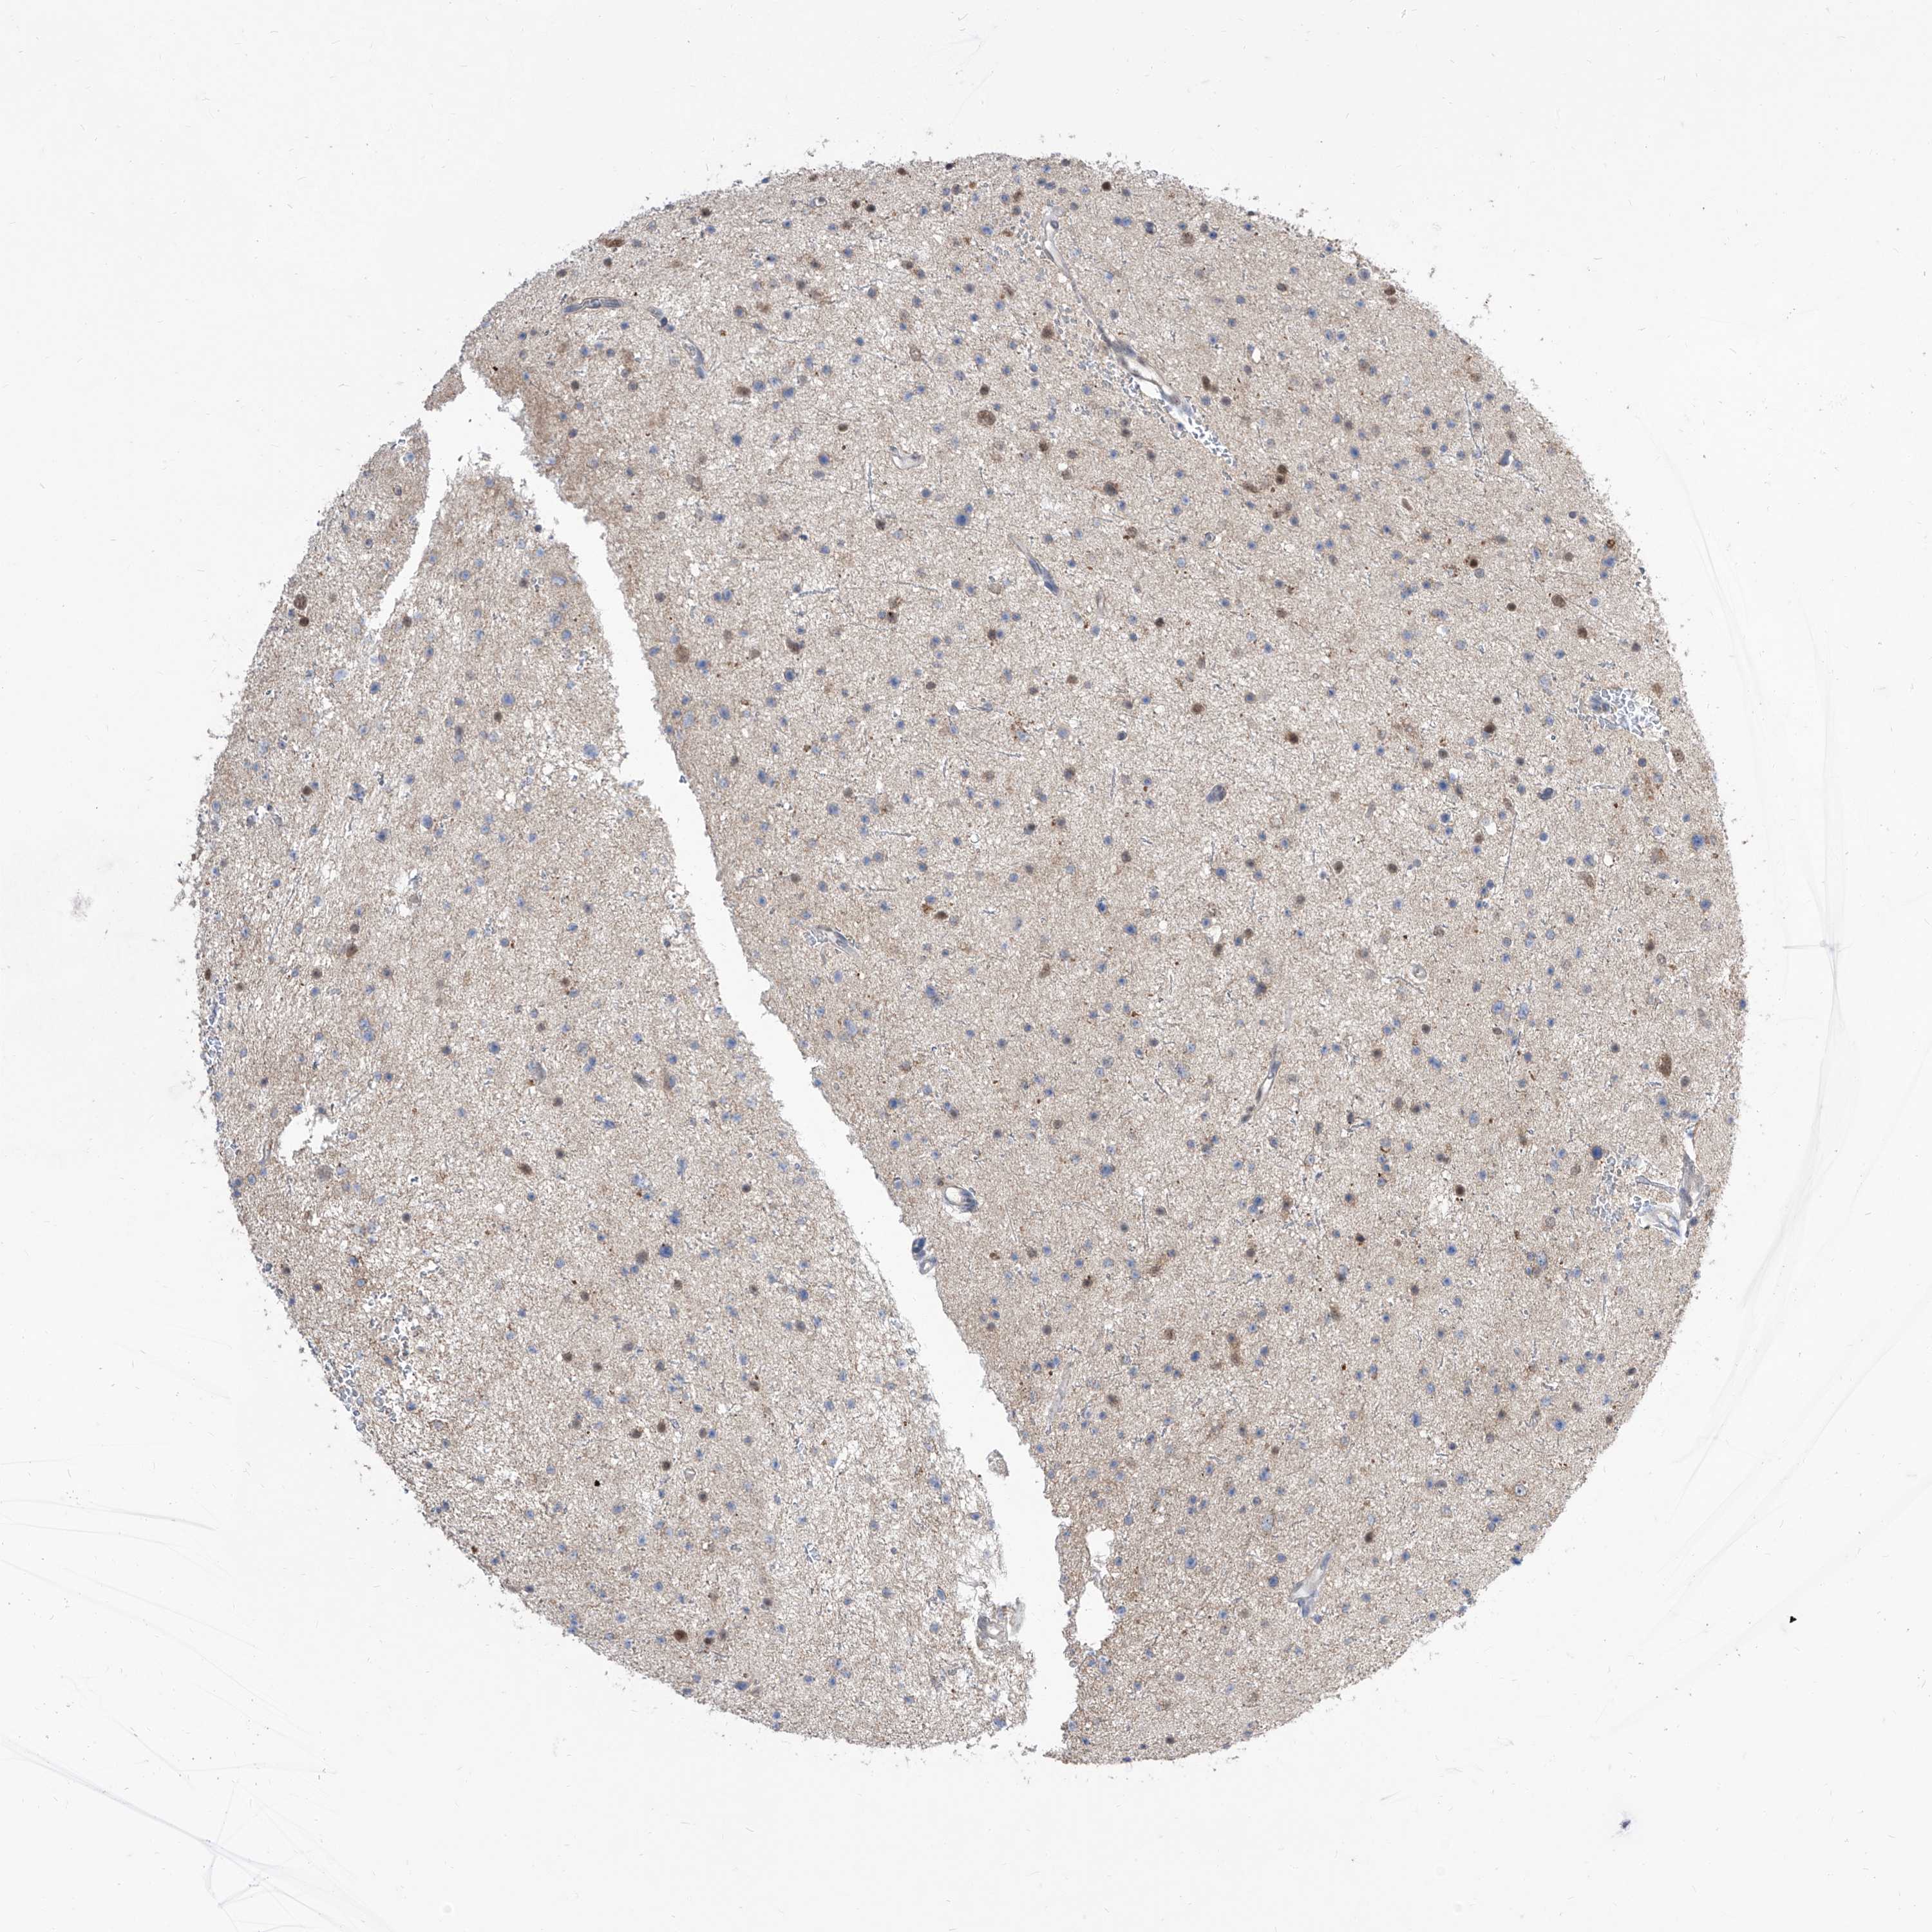

GLIOMA - Protein expressioni

A mouse-over function shows sample information and annotation data. Click on an image to view it in a full screen mode. Samples can be filtered based on level of antibody staining by selecting one or several of the following categories: high, medium, low and not detected. The assay and annotation is described here.

Note that samples used for immunohistochemistry by the Human Protein Atlas do not correspond to samples in the TCGA dataset.

Antibody stainingi

Antibody staining in the annotated cell types in the current human tissue is reported as not detected, low, medium, or high, based on conventional immunohistochemistry profiling in selected tissues. This score is based on the combination of the staining intensity and fraction of stained cells.

Each image is clickable and will lead to virtual microscopy that enables deeper exploration of all samples and also displays staining intensity scores, fraction scores and subcellular localization as well as patient and tissue information for each sample.

Antibody HPA031445

Staining

High

Medium

Low

Not detected

Intensity

Strong

Moderate

Weak

Negative

Quantity

>75%

75%-25%

<25%

None

Location

Nuclear

Cytoplasmic/membranous

Cytoplasmic/membranous,nuclear

Glioma, malignant, High grade

Glioma, malignant, Low grade

Glioblastoma, NOS